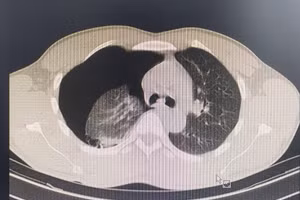

GD&TĐ - Bệnh viện Đa khoa Đức Giang (Hà Nội) vừa cấp cứu thành công nam bệnh nhân COVID-19 nguy kịch phải thở máy. Bệnh nhân là ông Đ.Q.T, 52 tuổi, trước đó có liên quan đến ổ dịch T&T trên địa bàn Hà Nội.